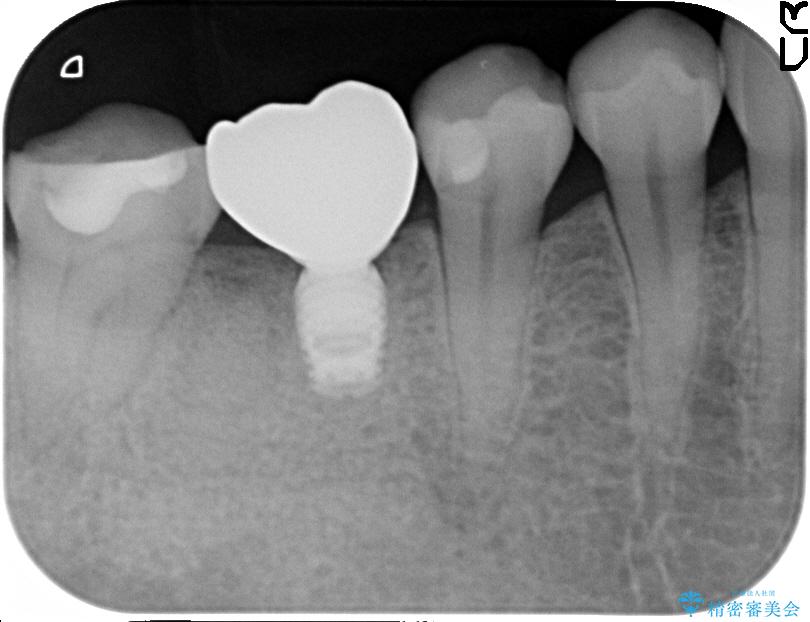

精密な検査を行ったところ、根が完全に折れている為、抜歯が必要となりました。抜歯後は骨と歯茎が痩せてしまう事がないように、人工の骨をつめ、インプラント治療を行う計画としました。

治療後について

抜歯を行った当日に骨の維持をする為、人工の骨を充填しました。インプラントを埋入する際には、ほとんどが自分の骨に置き換わっており、頬舌的なへこみを引き起こす事もなく、審美性・機能性ともに維持する事が出来ました。

また今回の治療では「バイコンインプラント」を使用する事により、インプラントの土台とセラミッククラウンを付ける際にセメントが全く残らないという利点を生かしたところ、見た目にも綺麗に仕上がり、患者様にも喜んでいただきました。

※下あごのインプラント治療の場合、ネジで止めるインプラントでは「ネジ止め用の穴」が少し見えてしまい審美性に欠けるデメリットがあります